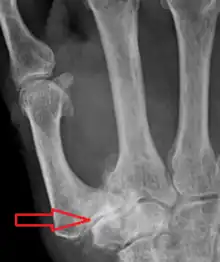

Stage 4 trapeziometacarpal osteoarthritis, with major subluxation of the joint.

Stage 4:

• Narrow joint space

• Concomitant scaphotrapezial arthritis